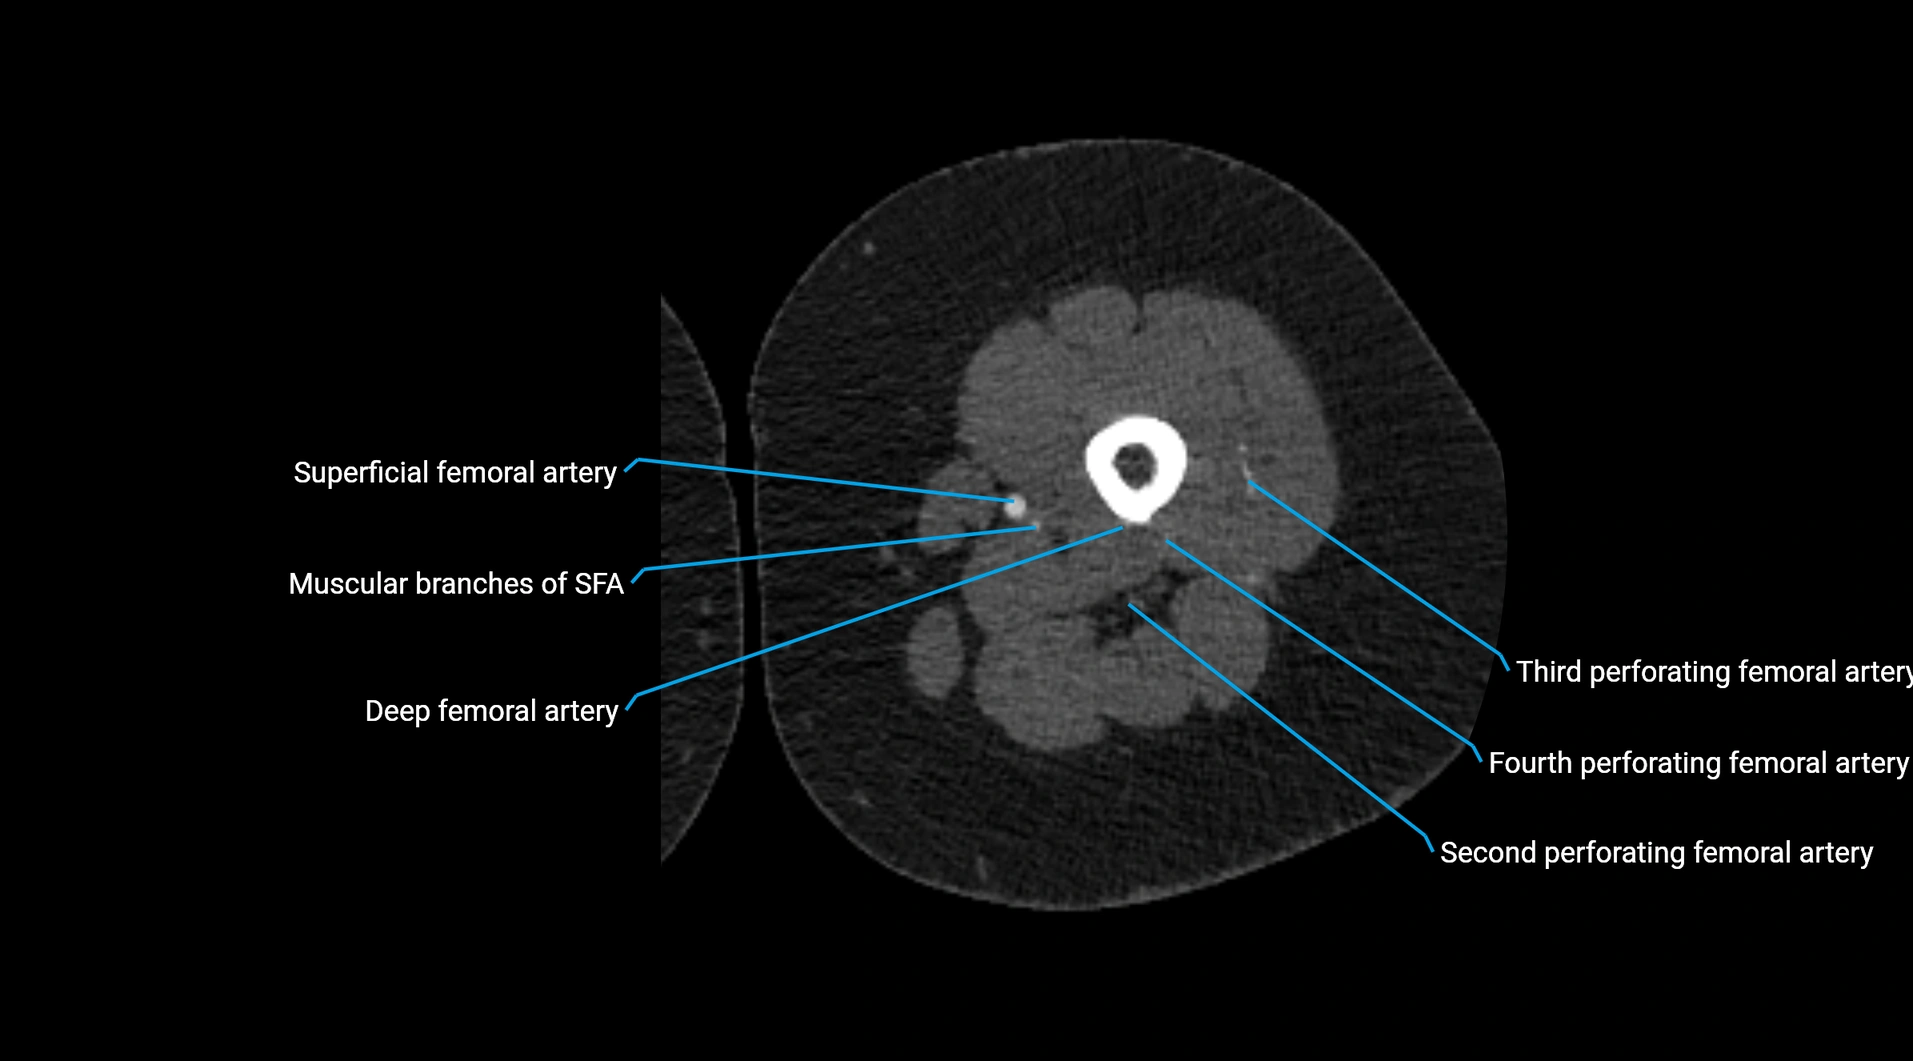

Contrast-enhanced CT (CTA):

• Gold standard for abdominal aortic imaging

• Provides excellent detail of lumen, wall, aneurysm, thrombus, and branch vessels

• Multiplanar and 3D reconstructions help in aneurysm measurement, stent graft planning, and dissection evaluation